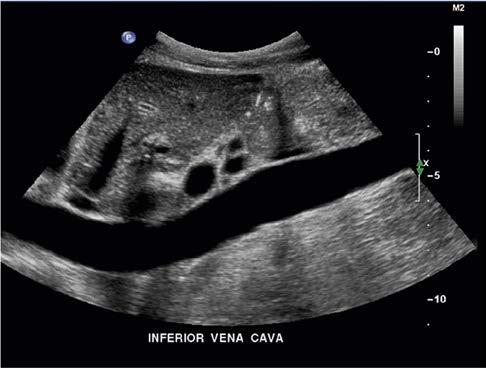

Doppler ultrasound has been used in diagnostic medicine for decades. Long-standing applications include monitoring the fetal heart rate during labor and delivery and evaluating blood flow in the heart and in the arteries and veins of circulation. Rapid scanning and processing of Doppler data

enable color-coded 2D and 3D presentations of Doppler information (color-Doppler displays) to be superimposed on gray-scale anatomic images (Figure 1-13). Doppler information is applied to loudspeakers for audible evaluation and to spectral-Doppler displays for quantitative analysis (Figure 1-14). The spectral-Doppler operation includes

anatomic imaging to determine the location(s) from which the spectral information is acquired (Figure 1-15).